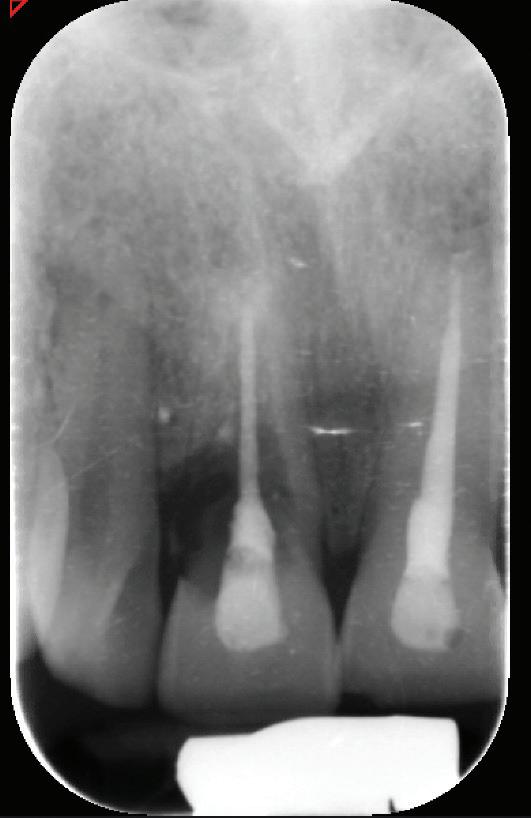

De asemenea, trebuie evaluate anual modificările radiografice. În ședința de inserție a restaurării, se înregistrează o radiografie bitewing standardizată pentru a permite evaluarea anuală a modificărilor osoase din jurul implantului. Remodelarea osului alveolar în primul an este bine documentată și depinde de tipul de implant utilizat; cu toate acestea, nu ar trebui să apară apical de primul filet al implantului. Prin urmare, este importantă abilitatea de a vizualiza filetele implantului pe radiografii. Modificările pierderii osoase de 2 mm sau mai mult după primul an reprezintă un semn de periimplantită. De îndată ce pierderea osoasă este recunoscută, pacientului trebuie să i se recomande terapia imediată pentru a opri procesul de boală.

SITE AUGMENTATION Reconstituirea țesutului moale periimplantar și papilar în zona estetică

RECONSTITUIREA țesuturilor moi periimplantare. Scopul acestui raport de caz este de a demonstra procedurile chirurgicale utilizate pentru corectarea unui defect al țesuturilor moi periimplantare folosind țesutul moale interdentar în combinație cu tuberozitatea ca locație donatoare de țesut conjunctiv, utilizând o abordare prin tunelizare într-o zonă estetică.